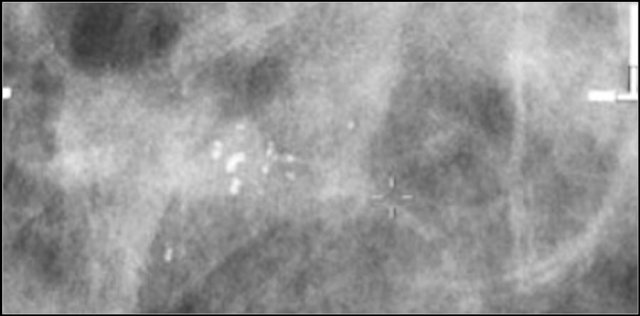

Study the images and describe the calcifications.

Then continue reading.

The findings are:

- Morphology: some are coarse heterogenous and some look more like fine pleomorphic.

- Distribution: Some calcifications are in a group ( <2cm) and some are in a regional distribution ( >2cm), but not in a segmental or linear arrangement.

This proved to be multifocal DCIS with areas of invasive carcinoma.